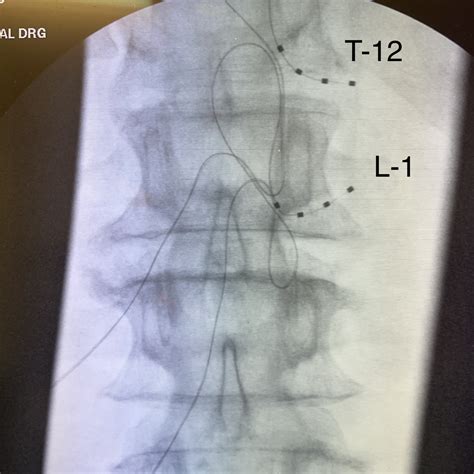

DGS involves the implantation of a small device that delivers electrical impulses to the dorsal root ganglion. The procedure typically includes the following steps:

• Implantation Surgery: The device is surgically implanted near the targeted dorsal root ganglion. This minimally invasive procedure is usually performed under local anesthesia.